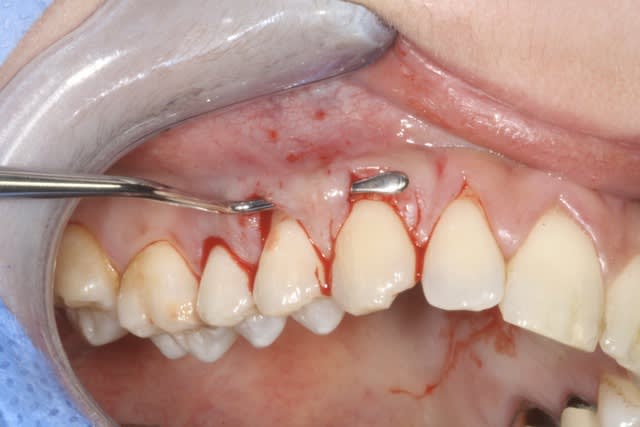

Pour boucler un fils commencé un peu plus haut voila la cicat.

Tunnel+ conjonctif tracté

Img 1725 ucxbs7 - Eugenol

Img 1743 dapqfw - Eugenol

Img 1809 yb92go - Eugenol